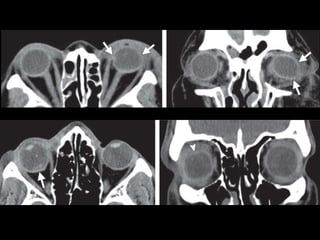

NOE

NOE • Clasificación deMarkowitz – Tipo I: segmento central único, sin compromiso del canto interno. – Tipo II: segmento central conminuto, sin compromiso del canto interno. – Tipo III: segmento central conminuto, con desinserción del canto interno.